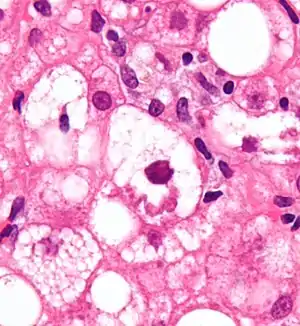

Mallory bodies are highly eosinophilic and thus appear pink on H&E stain. The bodies themselves are made up of intermediate cytokeratin 8/18 filament proteins that have been ubiquinated, or bound by other proteins such as heat shock proteins, or p62/Sequestosome 1.[5]

Micrograph showing a Mallory body. Original magnification 400X. H&E stain.